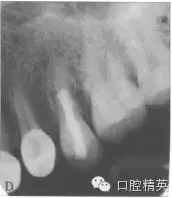

10個(gè)月后復(fù)查,頰側(cè)黏膜色澤正常(圖5),患者咀嚼正常,無不適。X線片示:根管斷端見MTA致密影像,根中側(cè)暗影減?。▓D6)。錐形束CT示斷端處MTA連接良好,斷端兩側(cè)已有骨質(zhì)形成(圖7)。

圖6 l0個(gè)月后復(fù)診時(shí)X線片。